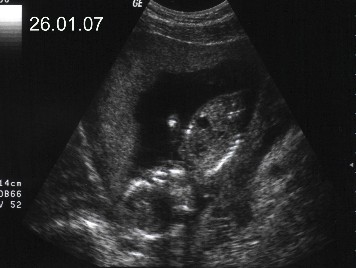

28.12. haben sie mich dann auf dem Monitor beim Ultraschall gesehen, ups ich war ja schon fast 3 Monate.....

Die Zeit verging......

7 Monate später...